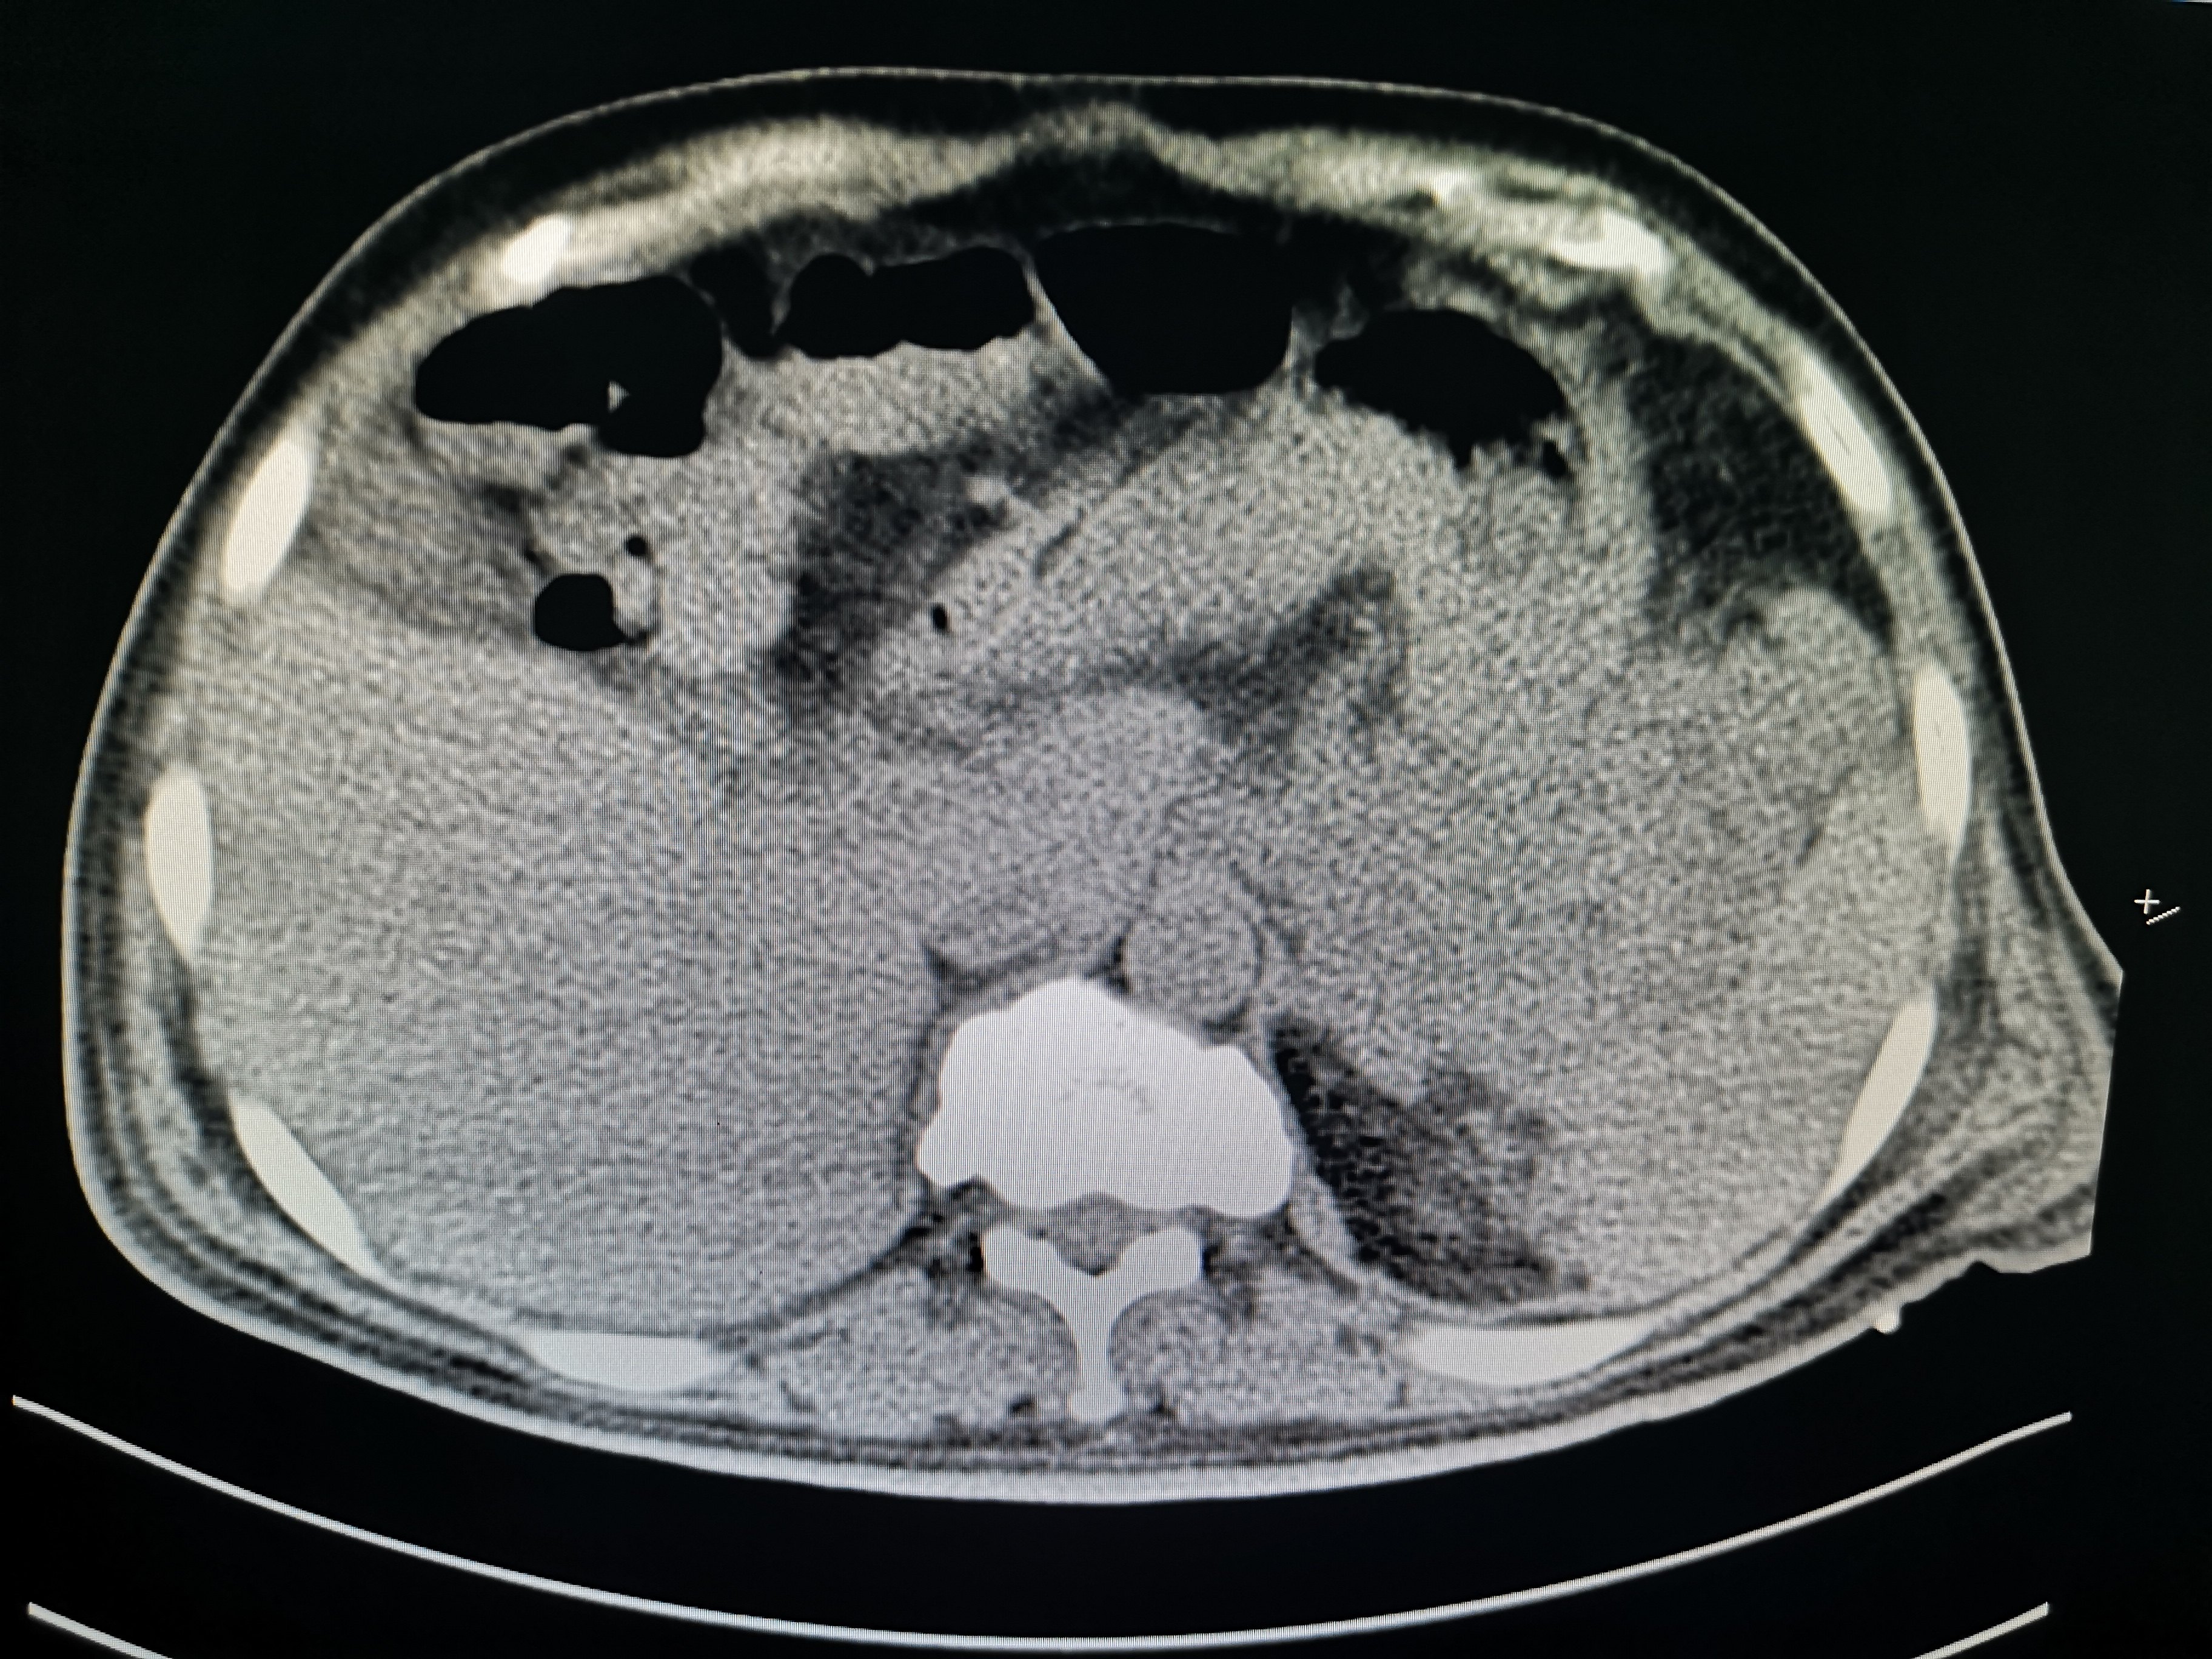

坏死性急性胰腺炎的影像诊断和治疗

坏死性胰腺炎 胰腺假性囊肿 胆囊结石